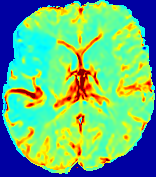

Figure 3: PIANO feature maps for one stroke patient, where the lesion is located in the left hemisphere. Top row: segmented stroke lesion region (white) on different slices, obtained from ISLES 2017. The corresponding slices for the PIANO feature maps are shown in the following rows.

For a better insight into an estimated velocity field 𝐕𝐕{\bf{V}} and diffusion field 𝐃𝐃{\bf{D}}, we compute the following maps: (1) 𝐕rgbsubscript𝐕𝑟𝑔𝑏{\bf{V}}_{rgb}: Color-coded orientation map of 𝐕=(Vx,Vy,Vz)T𝐕superscriptsuperscript𝑉𝑥superscript𝑉𝑦superscript𝑉𝑧𝑇{\bf{V}}=(V^{x},V^{y},V^{z})^{T}, obtained by normalizing 𝐕𝐕{\bf{V}} to unit length and mapping its 3 components to red, green, blue respectively; (2) 𝐕2subscriptnorm𝐕2\|{\bf{V}}\|_{2}: 222 norm of 𝐕𝐕{\bf{V}}; (3) D𝐷D: scalar field in Eq. 5.

Fig. 3 and Fig. 4 show the PIANO feature maps estimated from two ISLES 2017 patients: all are highly consistent with the lesion in both cases. Details of the blood flow trajectories are revealed in 𝐕rgbsubscript𝐕𝑟𝑔𝑏{\bf{V}}_{rgb} by the ridged patterns and the sharp changes of colors in the unaffected (right) hemisphere, while the flat patterns appearing within the lesion provide little directional information about the velocity and indicate low velocity magnitudes. Velocity magnitudes are more directly visualized via 𝐕2subscriptnorm𝐕2\|{\bf{V}}\|_{2}, from which one can easily locate the lesion where 𝐕2subscriptnorm𝐕2\|{\bf{V}}\|_{2} is low. D𝐷D also indicates lower diffusion values in the lesion, though with less contrast potentially due to the fact that it captures the accumulated effect of CA diffusion at the voxel-level.